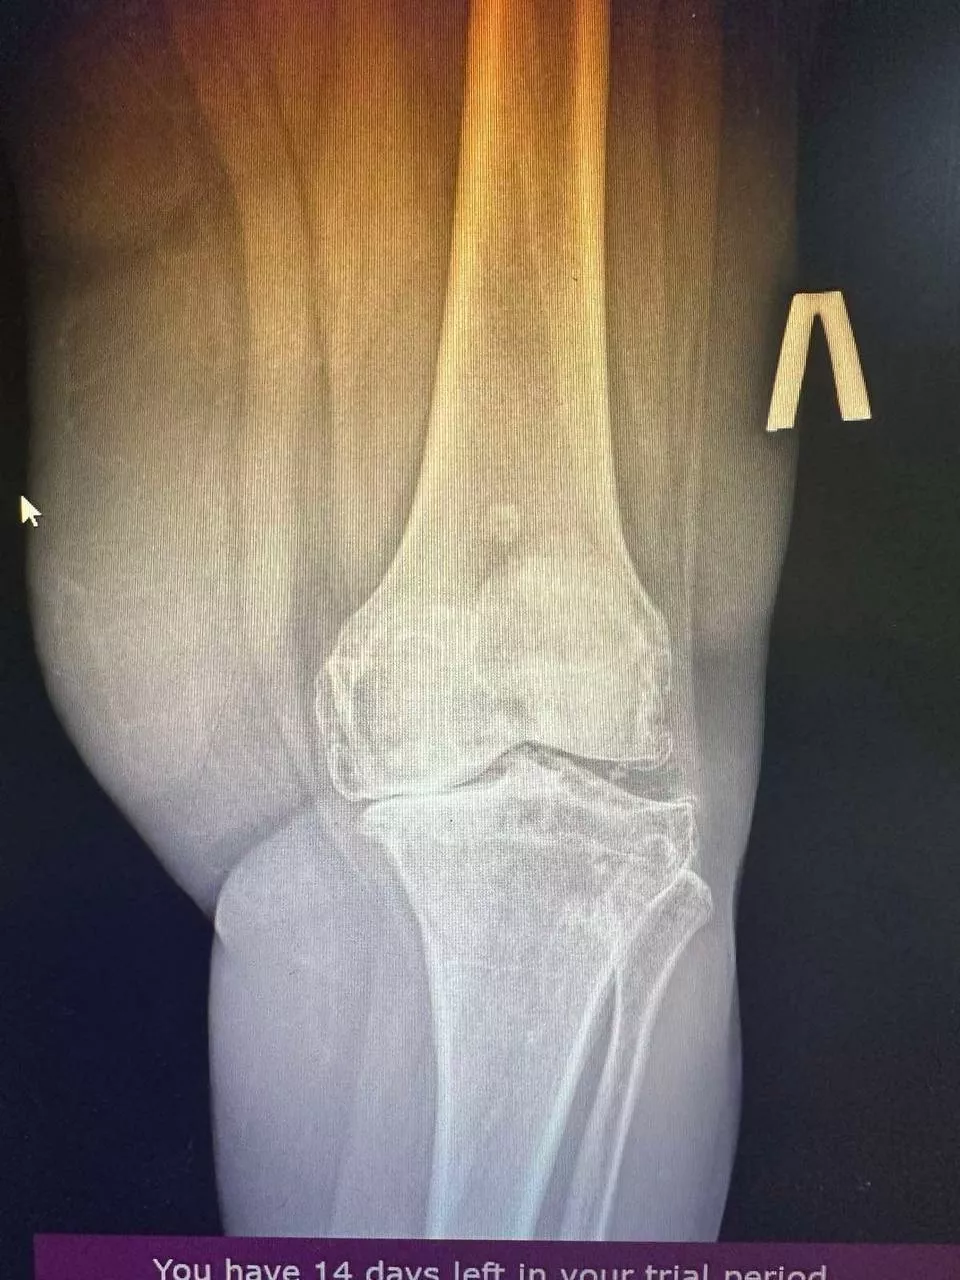

Ендопротезування колінного суглоба

Заміна колінного суглоба — операція, яку проводять у випадках, коли консервативне лікування не приносить результатів. Цей тип хірургічного втручання дає змогу замінити пошкоджений суглоб на штучний імплантат. Під час процедури усуваються джерела болю і відновлюється рухливість. У підсумку пацієнти можуть вільно рухатися і вести активний спосіб життя. Ендопротезування колінного суглоба дає змогу повернути якість життя на довгі роки.

Ендопротезування колінного суглоба — цю операцію призначають у разі значних ушкоджень колінного суглоба, які потребують повної заміни. Вона допомагає повністю позбутися болю і відновити рухливість. Підходить пацієнтам з важким артритом або значною деформацією колінного суглоба.